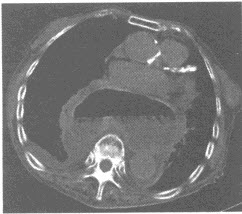

男性,45岁。突然左侧肢体活动不灵1天,伴恶心、呕吐,无发热。既往有高血压病史。

(单选题)CT检查如图所示,病变主要累及()

A:颞、枕、顶、额叶及基底节区

B:右颞、枕叶

C:右颞、顶叶

D:右颞、枕、顶叶

E:右颞、枕叶及基底节区